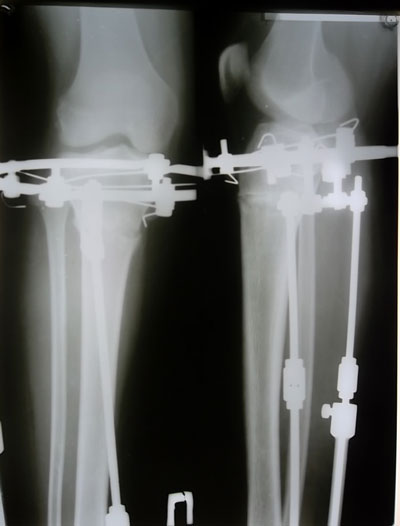

- Диагноз: О-образная деформация нижних конечностей

- Дата операции.: 13.06.2013

20 - ый день после операции.

Новое изобретение доктора Онипко - для смещения наружных мышц к внутреннему контуру.